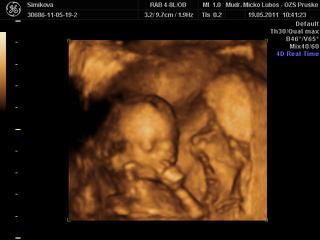

ahojte baby.tak som domaa som neopisatelne stastnaaaaa...babatko je v poriadku ma asi 16cm a vazi okolo 149g.som straassssnneeee radaaaaa. je to zazitok na cely zivot.stale tomu nemozem uverit ako krasne sme si to s malou pozerali.podla velkosti vychadza ten termin 11.11.je zdravucke a to som stastnaaaaaaaa. 😀 😀

no a co sa tyka pohlavia ... TEST KLAMAL 😠 cakame CHLAPCEKAAAAAAAAAA 😀 😀 😀

@lenka1108, super gratulujem 😎. Boli ste na 3-4D? Ak bolo uz vidiet pohlavie, tak zmenim nazor a pojdeme aj my 🙂. Pri prvom sme boli, ale az v 22 tyzdni a teraz sme si povedali, ze naco. Ale sme zvedavi na pohlavie... Tym testom chlapec / dievca neverim, tak som si to ani nerobila 😒